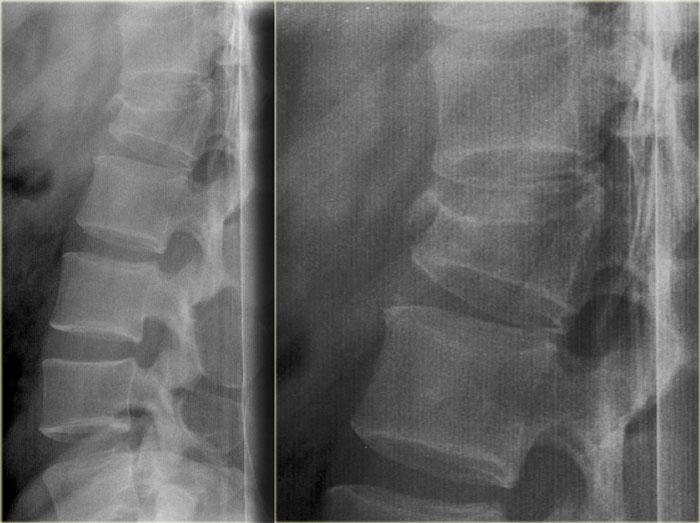

Hình ảnh bên trái của một nam giới 31 tuổi.

Anh ta đang làm việc trên mái nhà, ngã từ độ cao khoảng 5 mét và tiếp đất bằng hai chân.

Anh ta than phiền đau ở chi dưới bên trái và vùng thắt lưng.

Trước tiên hãy quan sát các hình ảnh, sau đó tiếp tục đọc.

Trên phim X-quang cho thấy tổn thương tăng gấp khúc của L1 với sự tổn thương cột trước và có thể tổn thương cột giữa.

Các tái tạo mặt phẳng đứng dọc trên CT cho thấy phần sau thân đốt sống có chiều cao bình thường, nhưng có một phần tổn thương ở phía sau thân đốt sống.

Hiện vẫn còn tranh luận về cách điều trị cho những bệnh nhân này và liệu MRI có vai trò gì trong những trường hợp này hay không.

Nếu đánh giá theo hướng tích cực, có thể gọi đây là tổn thương hai cột, đòi hỏi phải phẫu thuật cố định.

Nếu đánh giá theo hướng thận trọng, có thể gọi đây là tổn thương chỉ ảnh hưởng nhẹ đến cột giữa.

Bên trái là hình tái tạo theo mặt phẳng coronal và hình ảnh axial tại mức độ gãy xương.

Tiếp tục với MR.

Các hình ảnh MRI cho thấy phù tủy xương ở thân đốt sống bị tổn thương, nhưng không có tổn thương phần mềm bổ sung.

Dựa trên việc MRI không cho thấy bất kỳ phát hiện bổ sung nào, bệnh nhân này được điều trị như trường hợp tổn thương một cột.

Tham khảo ý kiến phẫu thuật chỉnh hình khuyến nghị điều trị bảo tồn với nẹp TLSO.

Ngày nay có xu hướng điều trị bảo tồn các chấn thương cột sống ngực-thắt lưng này, ngay cả khi có tổn thương nhẹ ở cột giữa.

Vai trò của MRI trong những trường hợp này vẫn chưa được xác định rõ ràng.